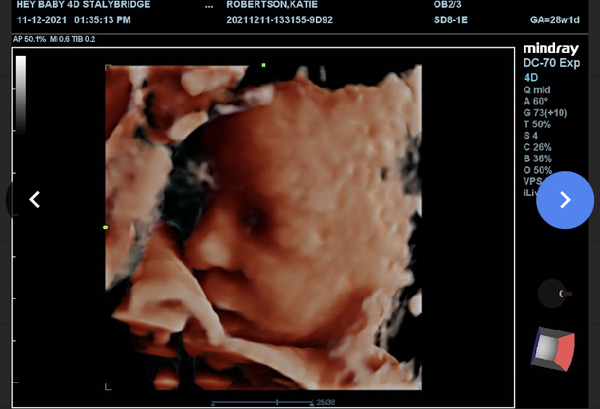

Kt1111 · 19/12/2021 21:51

29 weeks and 2 days now- she got fed up at the 4d scan and put her hand on o cover her face - I love the hbd a foot pic. ♥️ I hope you ladies get some good news soon! Xx